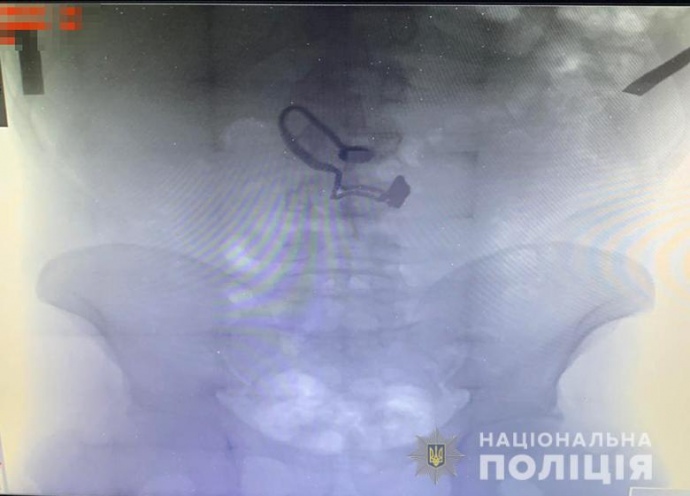

Під час поверхневого огляду у чоловіка знайшли гаманець потерпілої. Згодом він зізнався поліцейським, що зірваний ланцюжок проковтнув.

"Під час медогляду на рентген знімку затриманого лікарі виявили прикрасу", - відзначили у поліції.